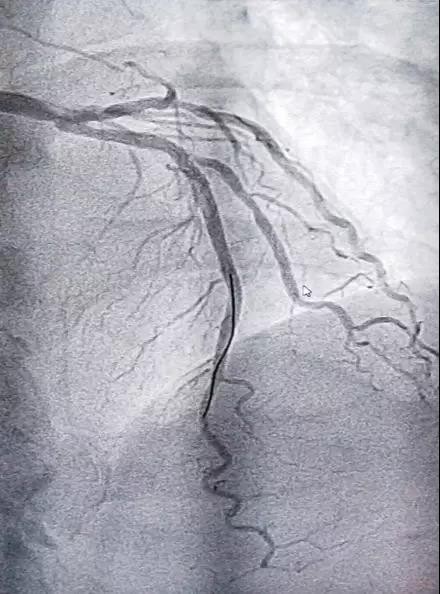

今年71岁的男性患者,有冠心病病史,因近3天无诱因出现胸痛、胸闷到德宏友谊医院就诊,经行冠状动脉造影术显示:患者冠脉病变堵塞严重,冠状动脉粥样硬化性心脏病LM远端狭窄60%,LAD近中段弥漫性病变,最狭窄处75%,D1开口处狭窄60%,患者情况十分危急。经与患者家人沟通,立即行冠状动脉支架植入术,成功在病变处植入支架,支架植入后血管再通效果良好,患者术中状态良好,术后胸闷症状有明显改善。